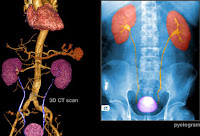

Imaging

tests, such as ultrasound or CT scans (seen here), can help reveal an

ovarian mass. But these scans can't determine whether the abnormality is

cancer. If cancer is suspected, the next step is usually surgery to

remove suspicious tissues. A sample is then sent to the lab for further

examination. This is called a biopsy. Sometimes a sample taken with a